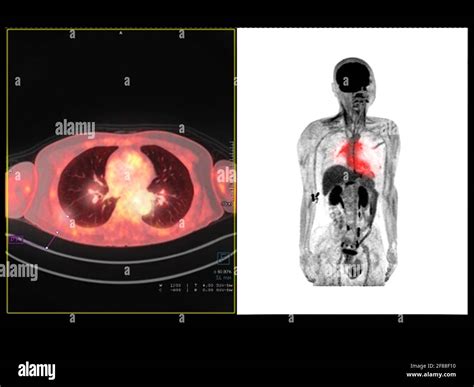

In the realm of medical imaging, the Pet Scan Image stands out as a powerful tool for diagnosing and monitoring various diseases. Positron Emission Tomography (PET) scans use radioactive tracers to produce detailed images of the body's internal structures and functions. These images provide invaluable insights into metabolic processes, making them particularly useful in oncology, neurology, and cardiology.

A Pet Scan Image is created by injecting a small amount of radioactive tracer into the body. This tracer emits positrons, which collide with electrons in the body, producing gamma rays. The PET scanner detects these gamma rays and constructs a three-dimensional image of the body's internal activity. The resulting images highlight areas of high metabolic activity, which can indicate the presence of disease.

• Oncology: PET scans are widely used to detect and stage cancer. They help identify cancerous tumors and determine the extent of the disease, aiding in treatment planning.

For example, in oncology, areas of high metabolic activity on a Pet Scan Image may indicate the presence of cancerous tumors. In neurology, abnormal patterns of tracer uptake can help diagnose conditions like Alzheimer's disease or epilepsy.

• Hybrid Imaging: Combining PET with other imaging modalities, such as CT or MRI, provides a more comprehensive view of the body's structures and functions. Hybrid imaging systems, like PET/CT and PET/MRI, offer improved diagnostic accuracy and treatment planning.